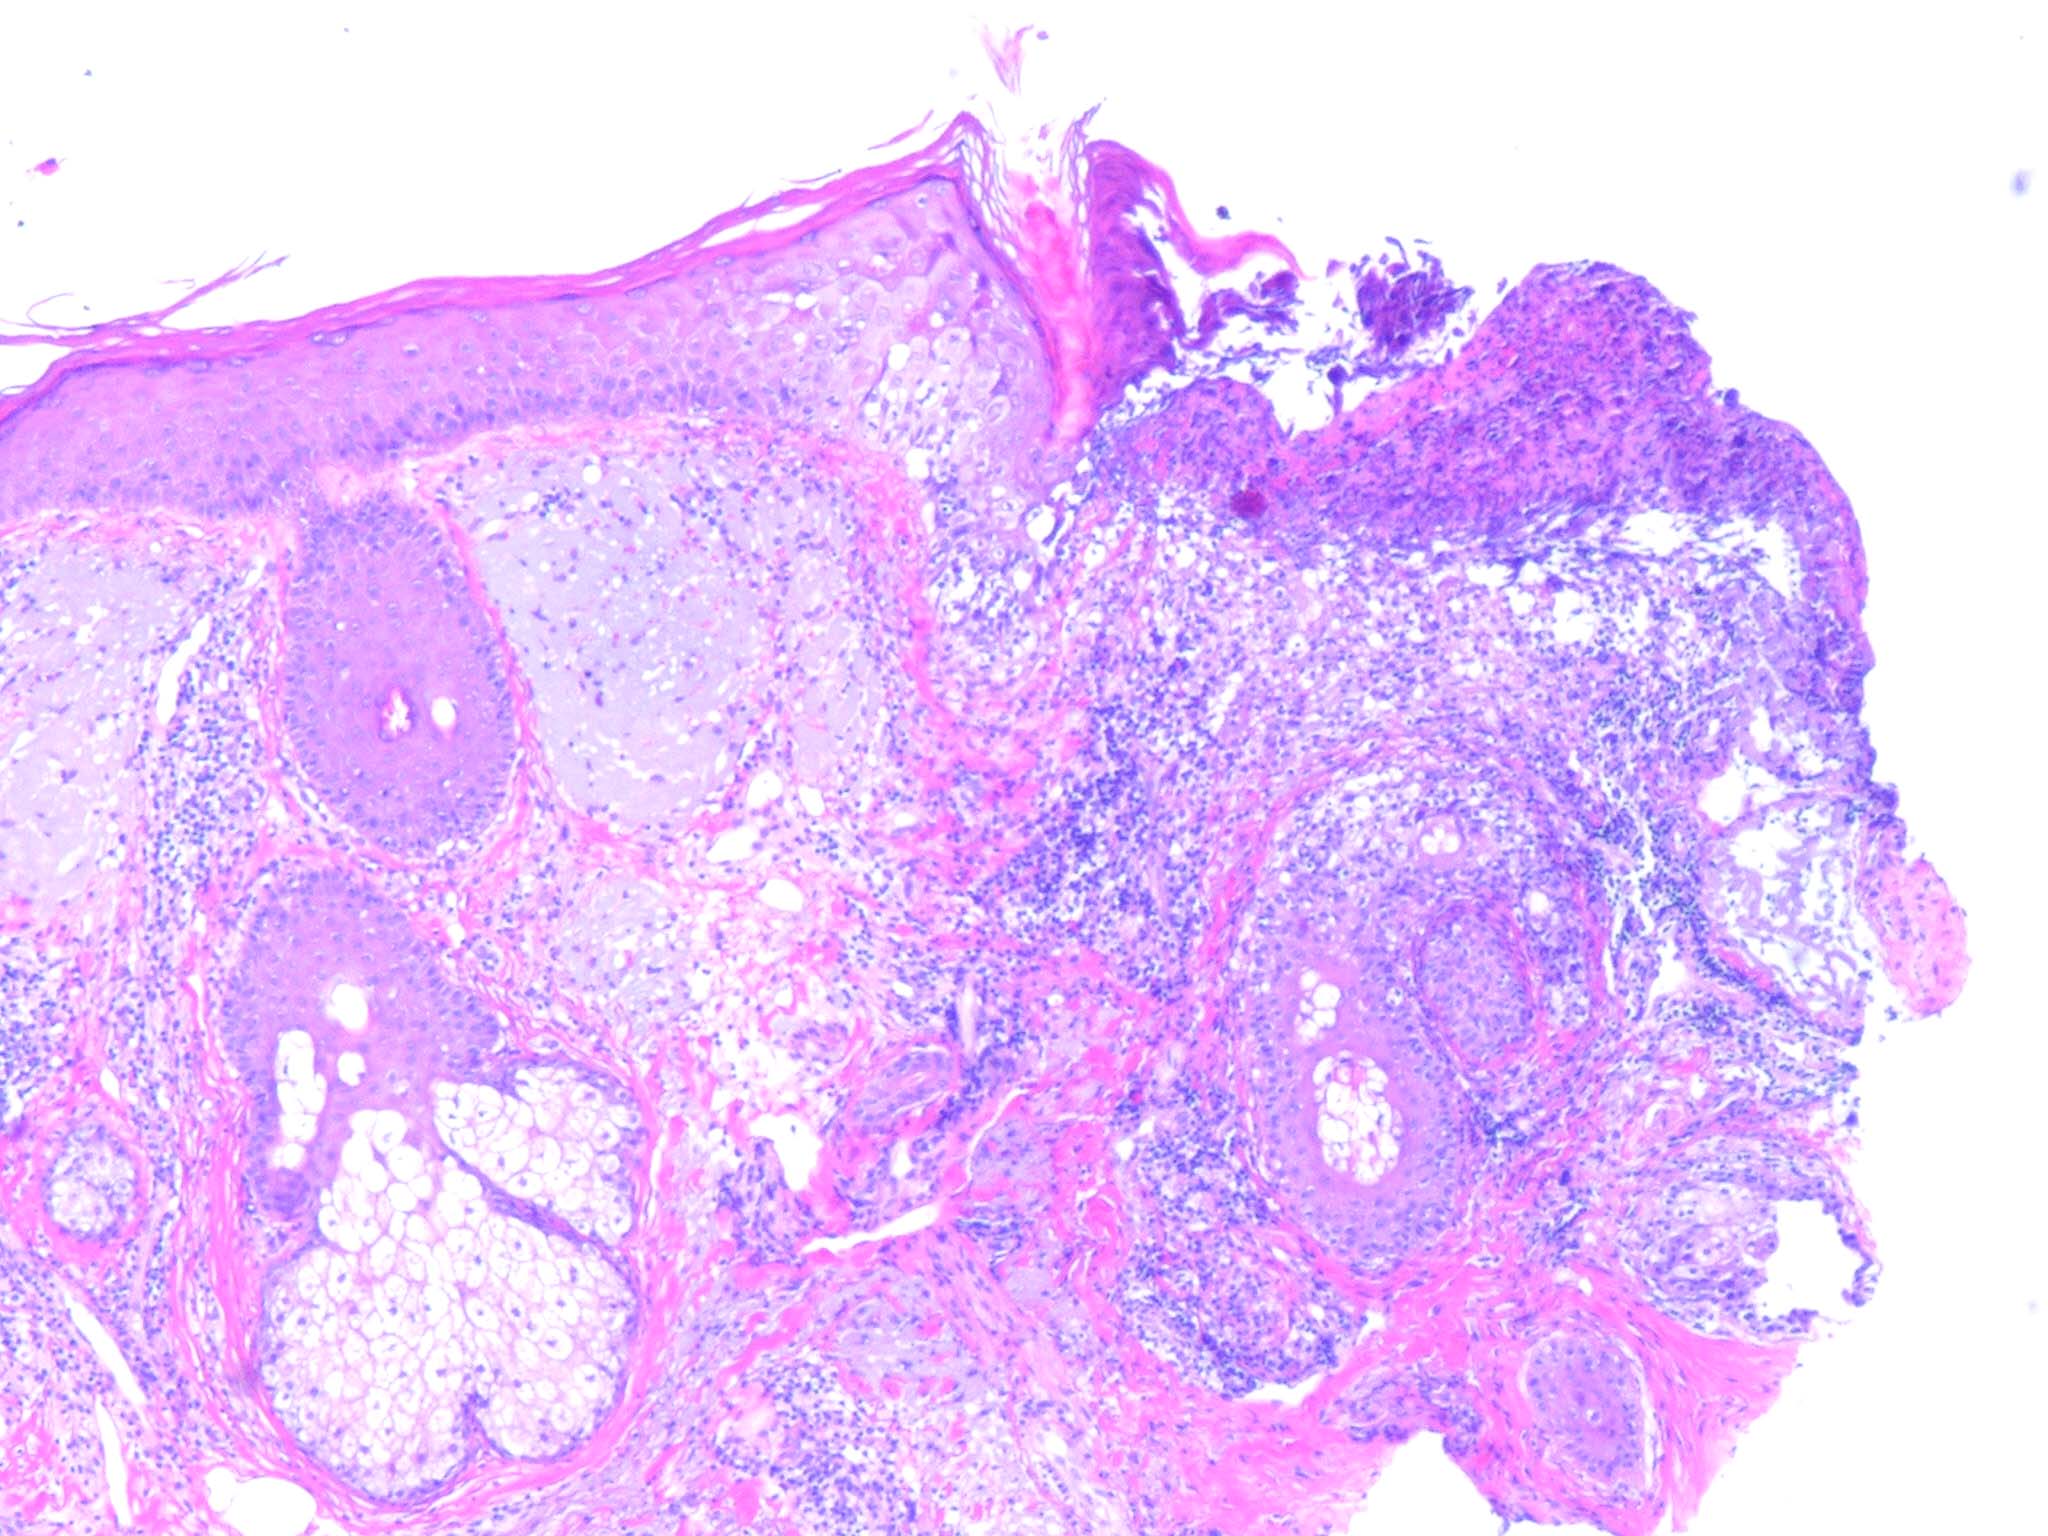

Herpes simplex = العقبول البسيط